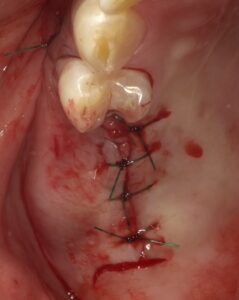

縫合を終えたところです。この場合では同時に

インプラントは埋入せず段階法としています。

約半年待ってからインプラントを埋入しました。